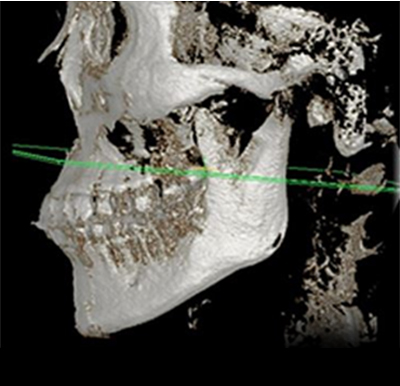

透過3D CT更精確分析,選擇適合每個人的矯正方法

採用最尖端的3D CT檢測,精確分析測量骨骼

· 引進快速掃描低輻射的Green16型裝置

· 三維立體式診斷3D CT裝置

· 骨骼精準診斷的面部輪廓矯正